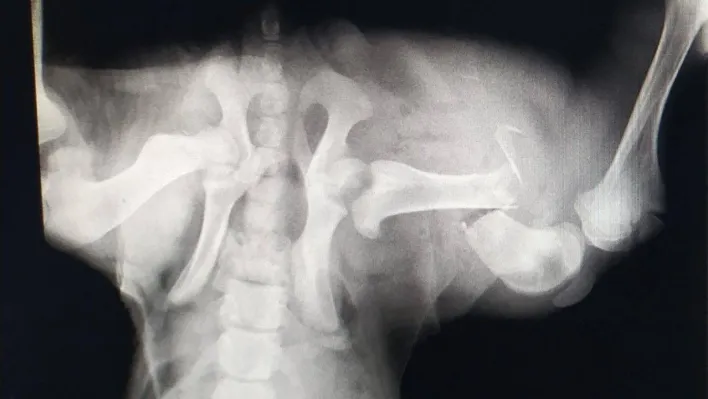

Edinilen bilgiye göre, İzmit’te trafik kazası geçiren sokak köpeği, bir vatandaş tarafından özel veteriner kliniğine götürüldü. Burada köpeğin genel durumunun çok kötü olduğu ve uyutulması gerektiği belirtildi. Ancak vatandaşın vicdanı el vermeyerek, sokak köpeğini Patilik Sokak Hayvanları Kasabasına getirdi. Patilik’te tetkiklerde köpeğin arka bacağında ciddi kırık bulunduğu belirlendi. Bursa Uludağ Üniversitesi Veteriner Fakültesi Cerrahi Anabilim Dalı Bölümünden Prof. Dr. Hakan Salcı’nın gözetiminde uzman hekimler tarafından kan tahlili yapılan ve röntgeni çekilen sokak köpeğinin ayağına plaka takıldı. Sokak köpeğine cerrahi operasyondan sonra ilaç tedavisi de uygulandı.

Patilik’ten yapılan açıklamada, "Patilik Mutlu Sokak Hayvanları Kasabasına getirilen ve arka sağ bacağında kırık bulunan sokak köpeği başarılı bir operasyon geçirerek sağlına kavuştu. Patiliğ’e ilk getirildiğinde hayati verileri çok düşüktü, 6 aylık kangal sokak köpeği Patilik’te tekrar hayat buldu" denildi.